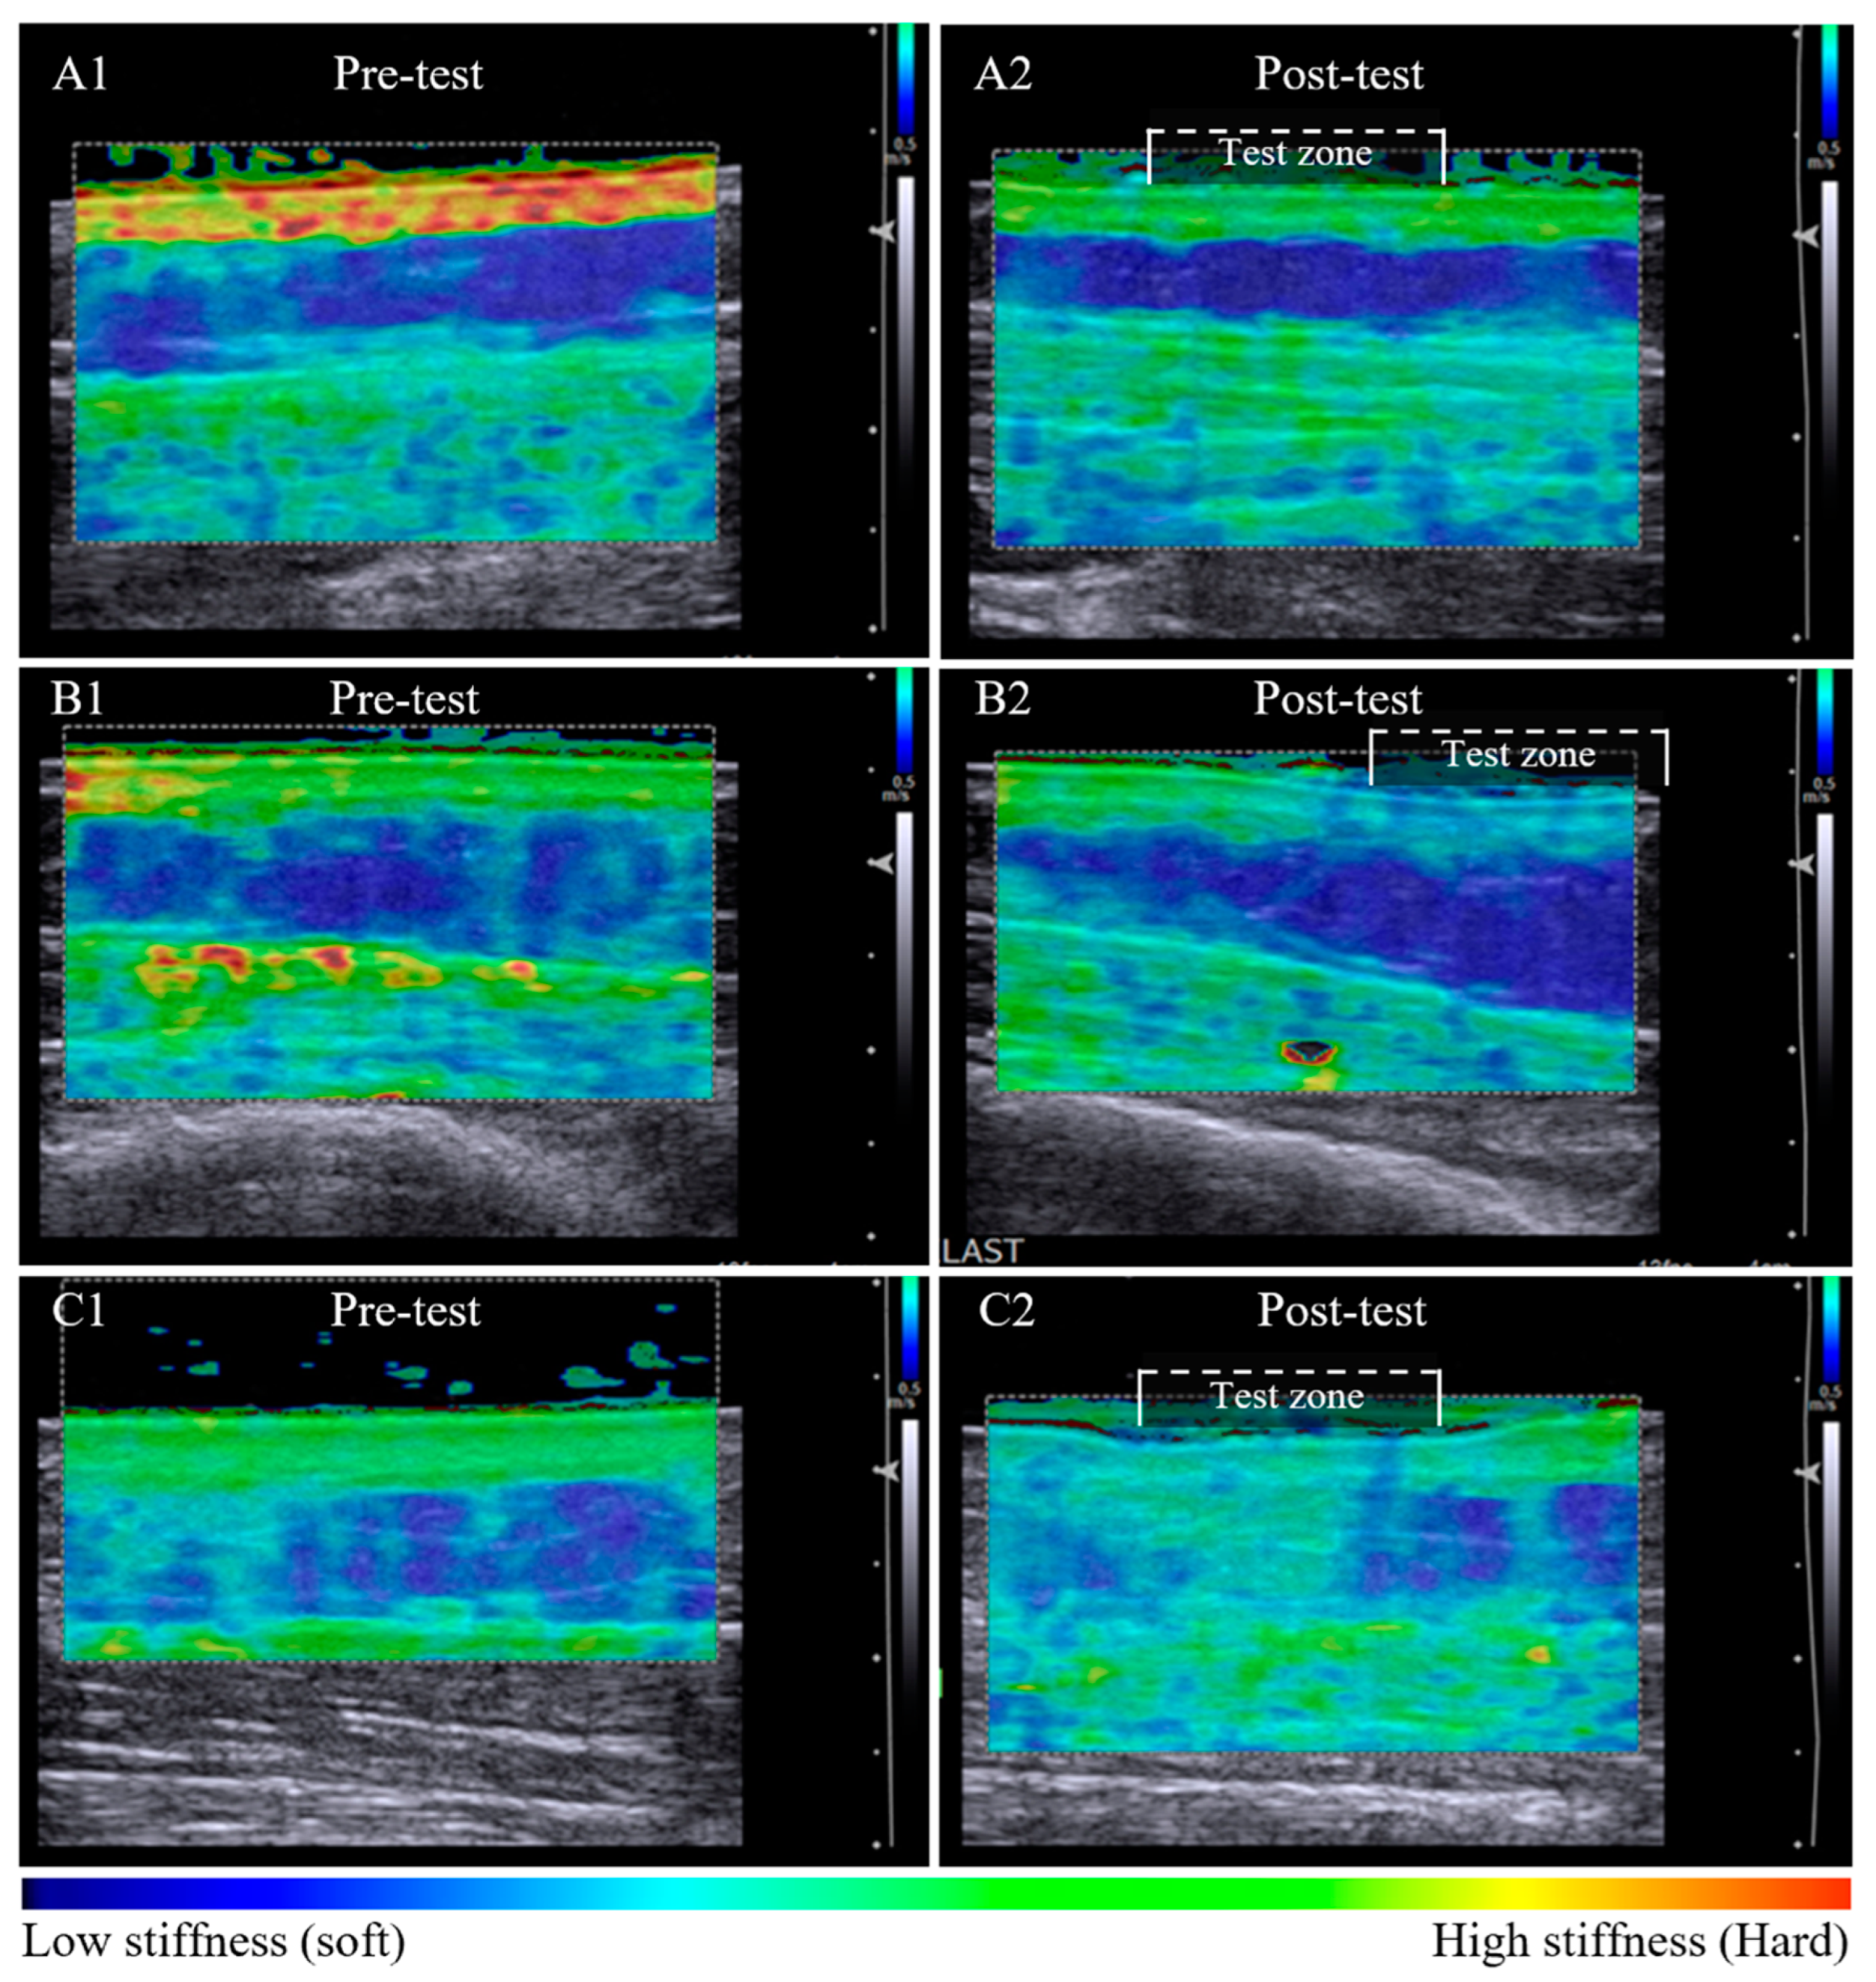

Elastography maps indicative of tissue stiffness distribution observed between unaffected and lymphoedema-affected tissue (posterior forearm, participant 11). The unaffected tissue is relatively homogenous in colour across the dermal and subcutaneous layers, with a tissue stiffness ratio of 1.38 (left panel). There is a difference in tissue stiffness between tissue layers of the lymphoedema-affected site with a tissue stiffness ratio of 2.69 (right panel). The subgroup analysis of seven sites compared elastographic imaging before and after a 60-s pitting test. In Figure 2, pre-test images for each series are similar, with a heterogenous elastographic map showing lymphoedema-affected dermal stiffness greater than subcutaneous stiffness.

Post-pitting test results indicate uncompressed tissue stiffness properties are altered with localised compression. Following the pitting test, the dermal tissue stiffness was lower at all sites (p = 0.018) while the subcutaneous stiffness either increased or decreased (not sig.) (Table 3). All tissue stiffness measures had changed from pre-test to post-pitting test, no sites or tissue layers remained the same within the test zone.

Tissue stiffness changes post-pitting appeared to relate to the appearance of the dermal-subcutaneous tissue layer border. A clearly defined tissue border was associated with retention of stiffness in the dermal layer post-pitting test. The dermal:subcutaneous stiffness pattern of the test zone appears similar to adjacent tissue (Figure 2A1,A2). A less defined border was associated with a local reduction in dermal stiffness within the test zone that is visibly altered compared to the reference tissue outside the test zone (Figure 2B1,B2). Loss in border definition was also observed in tissue with subcutaneous compositional change, whereby dermal stiffness reduced and subcutaneous stiffness increased within the test zone post-pitting test (Figure 2C1,C2).

Figure 2.

Pre-test and post-pitting test elastographic maps of lymphoedema-affected tissue. Lymphoedema-affected pre-test elastographic maps are heterogenic with high dermal stiffness (bright green) and relatively low subcutaneous stiffness (dark blue) (A1,B1,C1). Series A and B illustrate tissue stiffness reduction in both tissue layers post-pitting test. Stiffness is retained within the tissue layer where an intact border is apparent (A2), and the stiffness is altered within the test zone where there appears to be tissue border deterioration (B2). Tissue response was inconsistent among participants, with example (C2) showing a reduction in dermal stiffness and an increase in subcutaneous layer tissue stiffness post-pitting test, indicative of tissue compositional change.

Subcutaneous stiffness changes observed in this study corroborate earlier work by Righetti et al. (2007), who demonstrated that subcutaneous stiffness could increase or decrease with localised compression. Unlike other conditions, advancing stage and severity of lymphoedema does not result in a progressive increase in tissue stiffness [10]. Consistent with Righetti’s analysis [12], we propose the stress generated from the pitting test promotes a shift in extracellular fluid away from the test site, revealing discord in tissue stiffness within the tissue layers when compositional changes are present. We propose that any lymphoedema subcutaneous stiffness increase is due to fibrotic or fibro-fatty compositional change, and a decrease due to free-fluid or fatty composition. An increase in subcutaneous mechanical stiffness was most evident by comparing elastography maps and tissue stiffness before and after the pitting test.

The border integrity findings have great relevance to both clinicians and researchers for understanding the effects of interventions aimed at reducing lymphoedema. The post-pitting elastography images affirm the dermal-subcutaneous border as a possible indicator of tissue structural integrity that relates to tissue deformation from the pitting test. Previous authors have described the dermal-subcutaneous tissue layer border in early lymphoedema as a clear, bright line between the tissue layers in greyscale imaging [17] and suggest the border becomes less structurally organised as lymphoedema progresses [18]. However, border deterioration is also known to occur with cellulite deposition in non-lymphoedema tissues [19]. In our previous work, we reported border deterioration to occur inconsistently across lymphoedema-affected and non-lymphoedema presentations [13]. Border deterioration is marked by a reduction in the definition of the structural line and increasing size of border undulations and serrations [19] and has been associated with greater pitting depths [14]. Although research is yet to confirm all of the factors that influence border integrity, apparent loss in border definition has been shown to be clinically meaningful with respect to pitting depth and tissue stiffness change.

The dermal-subcutaneous border integrity was best demonstrated with pre-test and post-pitting elastography maps. An intact dermal-subcutaneous border resulted in the retention of tissue stiffness within the tissue layer boundaries in pre-test and post-pitting images. By contrast, the elastography maps of sites with border deterioration displayed reduced mechanical stiffness across tissue layers within the test zone in post-pitting images. The observation may indicate a change in structural strength of the border, however, we do not know the implications of this finding concerning tissue responsiveness to treatment, long-term outcomes, or lymphoedema progression. Further research is required to support the inference that there is clinical significance in tissue layer border integrity with respect to health outcomes.